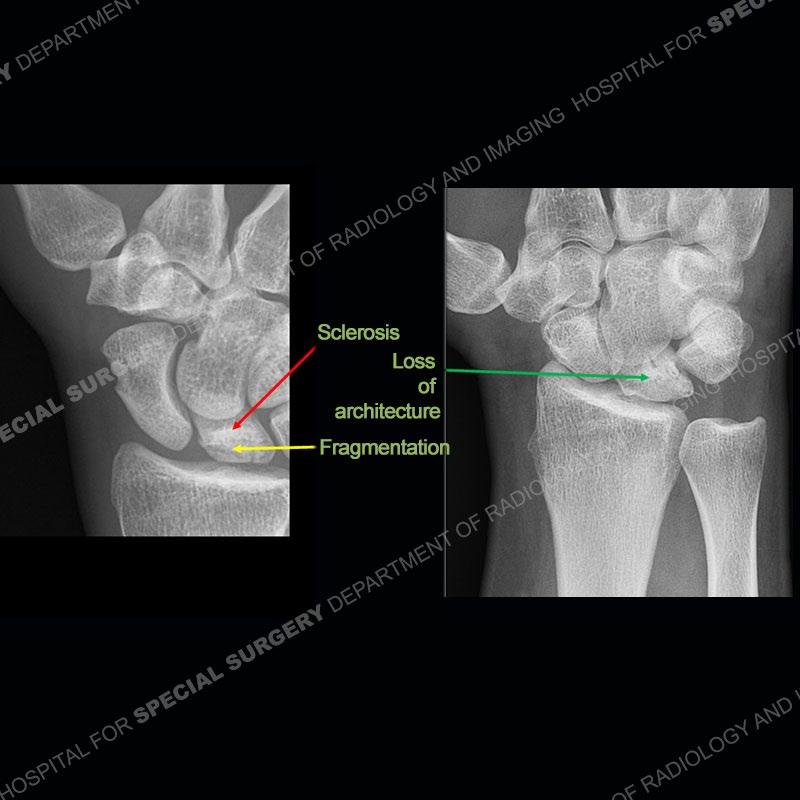

Both cases demonstrate similar findings to slightly less and more conspicuous degrees. The radiographs show sclerosis and fragmentation/collapse of the lunate. The CT images for case one just further clarify the architecture of the lunate. The MRI images show a slightly greater degree of variability but with overall persistent areas of low signal of the lunate on all pulse sequences and with a loss of the geometry of the lunate indicating collapse and fragmentation.

A well recognized but still poorly understood entity with necrosis and collapse representing the end stage of the pathology. The reasons for the necrosis are likely multifactorial and relate to the anatomy of the wrist inclusive of ulnar variance and the anatomy of the vasculature to the lunate. Other inflammatory, biological processes and overuse/trauma also likely play a role in the development of the necrosis. The disease manifests by sclerosis of the lunate followed by collapse and fragmentation. This is then followed by abnormal orientation of the scaphoid in a palmar flexed position and then adjacent arthritis. These latter processes were not the focus of this case presentation. The MRI will show areas of low signal on all pulse sequences indicating the areas of devitalized bone. The foci of slightly increased signal are in keeping with areas of maintained perfusion and highlight the variable architecture and findings of Kienbock’s. The fragmentation and collapse of the bone are seen well on both CT and MRI.